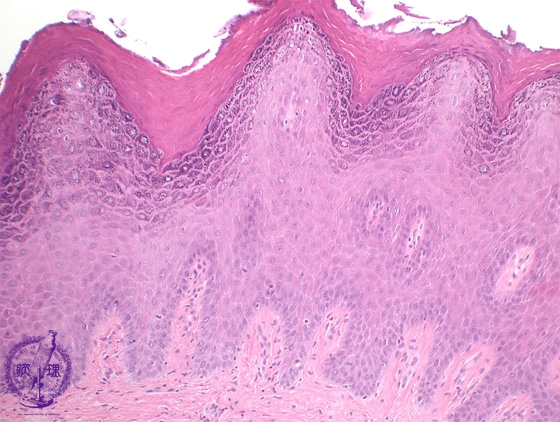

- (3)Oral mucosal diseases(★Leukoplakia:epithelial hyperkeratosis)

Microscopic finding (HE stain, intermediate and high-power view):The mucosa exhibits marked hyperkeratosis and hypergranulosis within the epidermis(*) but there is no cytological or architectural atypia.